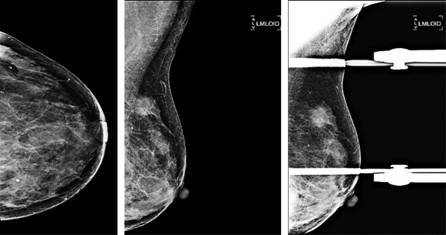

Se contó con 32 reportes de ultrasonido y mastografía, lo que corresponde al 55.17% de las pacientes con diagnóstico de cáncer de mama triple negativo. Los principales hallazgos fueron masa irregular (85%), bordes lobulados (65%), márgenes espiculados (15%), asimetría focal (25%), distorsión de la arquitectura (15%), microcalcificaciones (15%) y sin alteraciones (5%). En la Figura 2 podemos observar un ejemplo de una mastografía con una lesión ocupante triple negativo Figuras 2 y 3. En la Figura 4 podemos observar el hallazgo en un ultrasonido con cáncer ductal infiltrante poco diferenciado, característico del cáncer de mama triple negativo.

Figura 2: Femenino de 55 años, proyecciones mastográficas CC y MLO con una lesión ocupante de espacio en el cuadrante superior externo de la mama izquierda, Ca ductal infiltrante poco diferenciado. Inmunohistoquímica: RE (-), RP (-), HERB2 (-), Ki67 (50%), CD-34 (10-15), P-53 (100%).